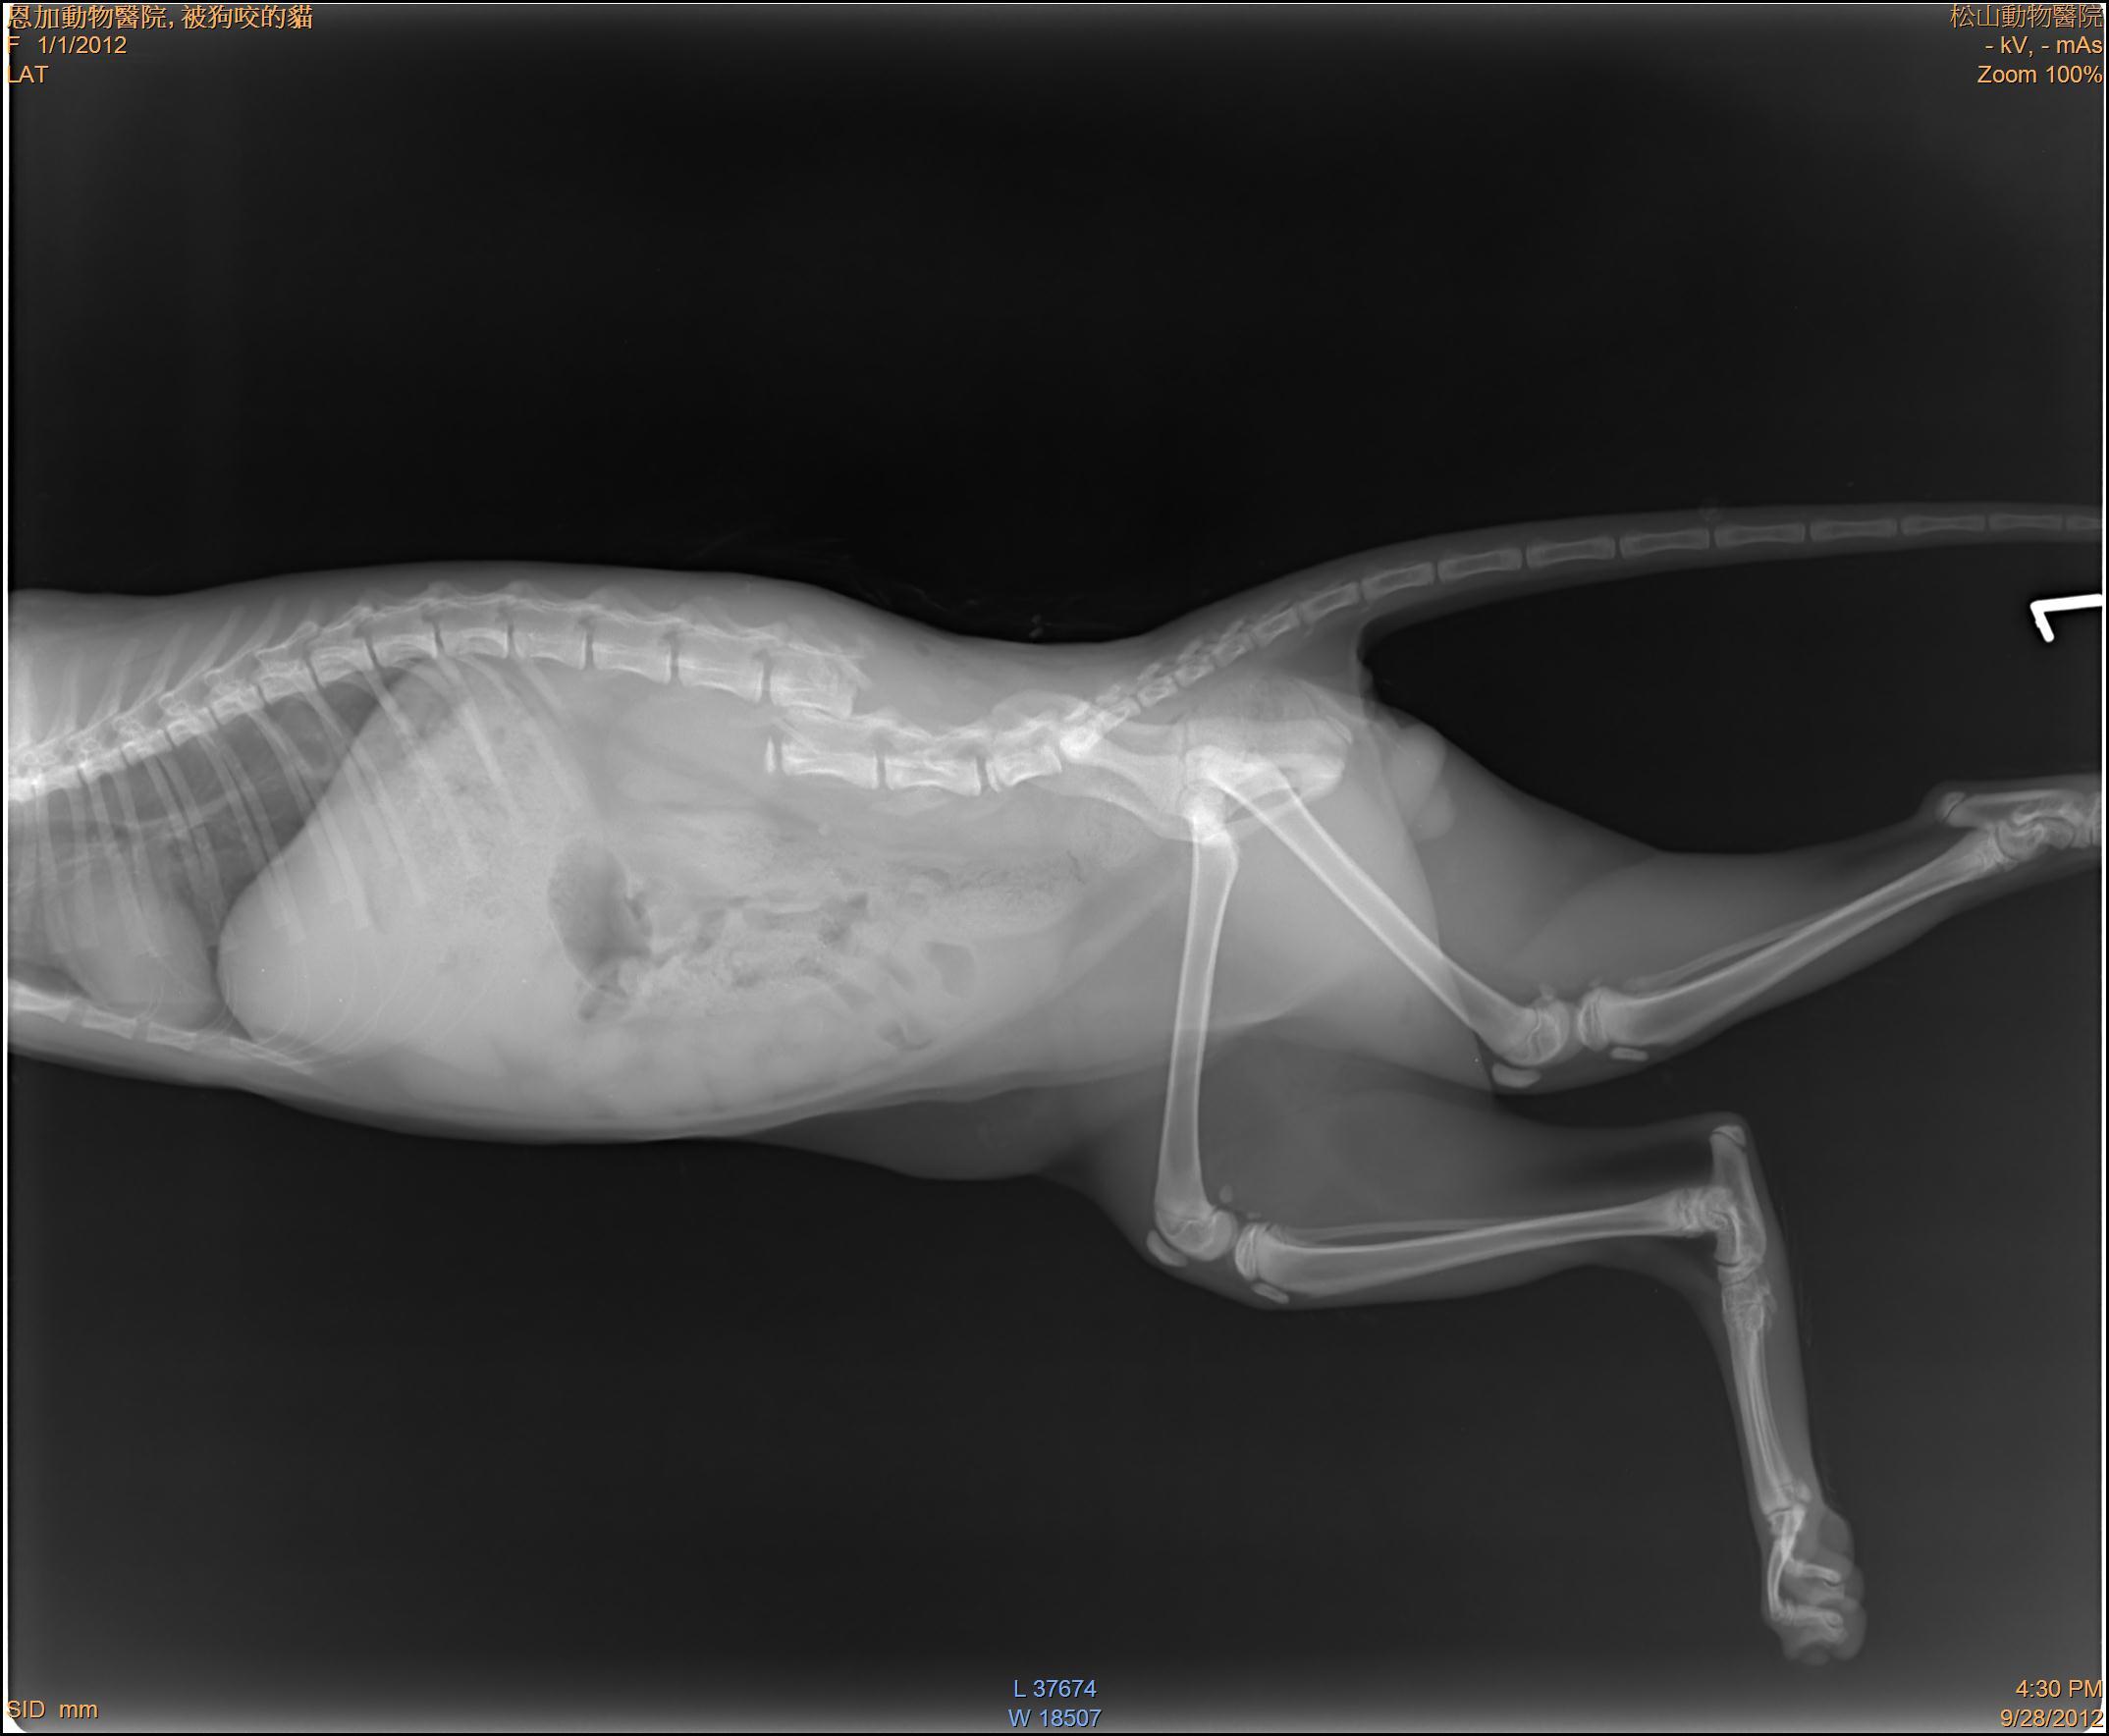

主題: 三清宮狗咬斷腰椎貓 申請者姓名: 岳丹楓 花色: 申請日期: 2012-11-07 15:17:35 申請者部落格: 申請者臉書網址: 所在縣市/合作醫院: 台北市/恩加動物醫院 治療費用: 18900元 需求人數: 20人 已結案 (2013-06-27 13:53:51) 報名人員: 婷(已付款)、桑尼(已付款)、Jennifer Su(已付款)、Kelly Chen(已付款)、Cecilia Shih(已付款)、Jimmy Li Li(已付款)、吉兒(已付款)、Min-Hua LI(已付款)、吳亭亭(已付款)、陳玲心(已付款)、Flora Chen(已付款)、curry0、yi(已付款)、timel0607(已付款)、海倫(已付款)、curry0(已付款)、curry0(已付款)、Elly(已付款)、Yu Chiu(已付款)、桂芳手藝行(小咪)(已付款)、周菁(已付款)、 候補人員: 肥美貓、 動物病情說明: 這是一隻在三清宮餵養的時候看到的受傷貓,因為這裡也有很多流浪狗,可能是附近的野狗咬傷的,受傷地方剛好是腰部有四個明顯的傷口,X光下可以看到腰椎整個斷裂,經過生命跡象穩定之後,雖然下半身已經癱瘓,但是看他那麼灑嬌的模樣,決定幫他做脊椎固定手術,以方便將來生存活動,現在他傷口都復原了,只是需要包尿布,他真的很撒嬌,叫人真的很捨不得,希望大家多多幫忙。